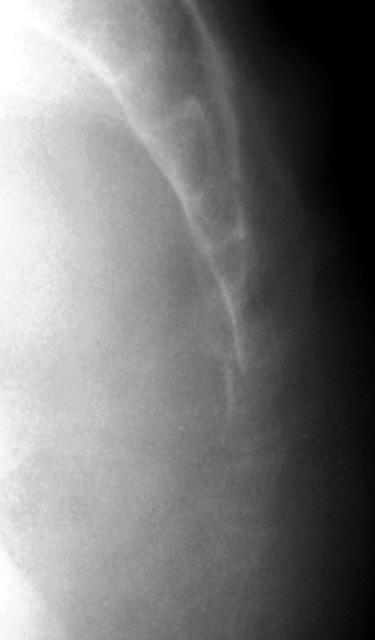

Случай № 3.

3. Перелом III пястной кости.

Случай №3: Перелом шейки 3 пястной кости, типа зеленой веточки.